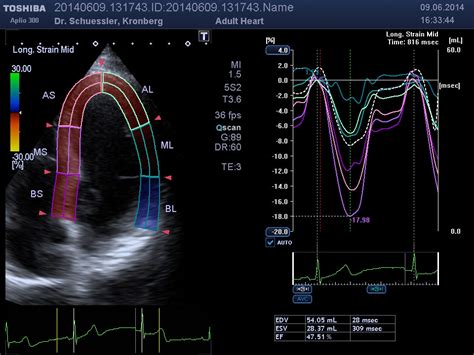

心电图读图(这是很多医学生初学的痛点 , 必须知道)首先得知道心电图各个波群的背后含义和表现特点:P波(心房活动):房性期前收缩 , 心房颤动 , 阵发性室上性心动过速QRS波(心室活动):室性期前收缩 , 室性心动过速 , 心室颤动PR间期(房室传导):房室传导阻滞QT间期:心室去极化和复极化全过程所需时间总和ST段、Q波:心肌梗死、心肌病等T波高尖:高钾血症、急性心肌梗死U波:低血钾知道各个波群的特点后 , 接下来 , 心电图读图的步骤主要分为三大步骤:第一、看心率 , 如图所示:RR间期